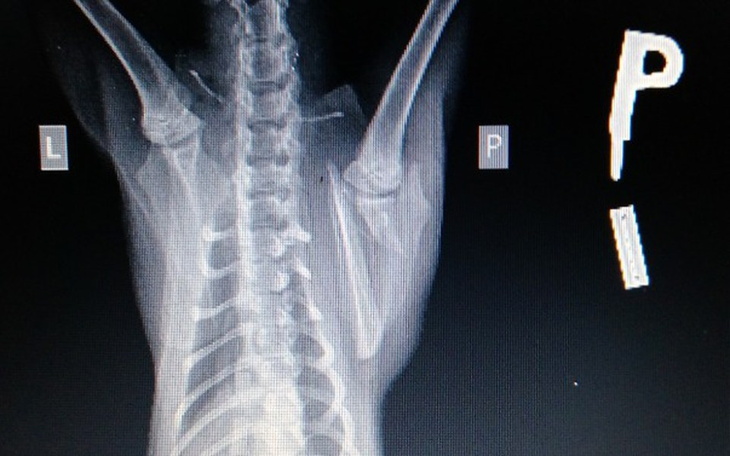

Wyrok : złamanie łopatki z przesunieciem, samo się nie zrośnie, trzeba operować.